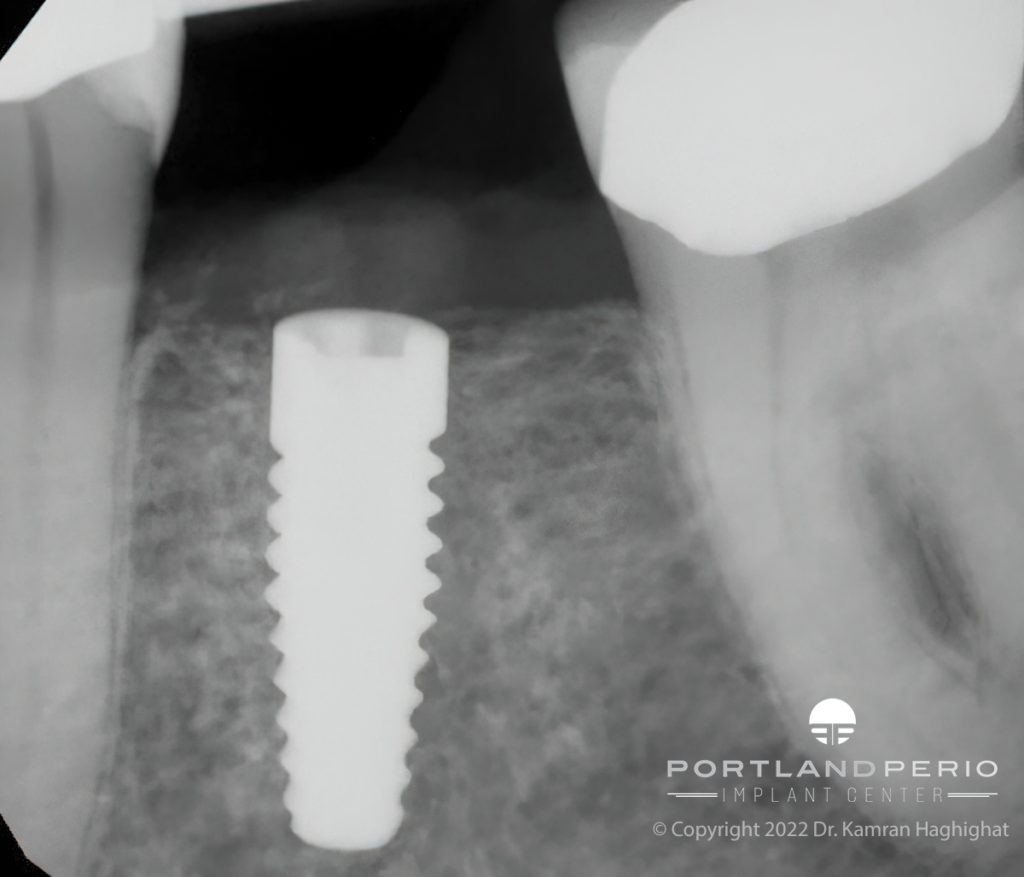

NobelPearl is designed to support a natural softtissue appearance. Its

NobelPearl™ a unique 100 metalfree twopiece ceramic implant

Nobel Biocare NobelPearl Tapered Dental Implant SpotImplant

NobelPearl™ Ceramic Dental Implants PPIC

NobelPearl™ Nobel Biocare